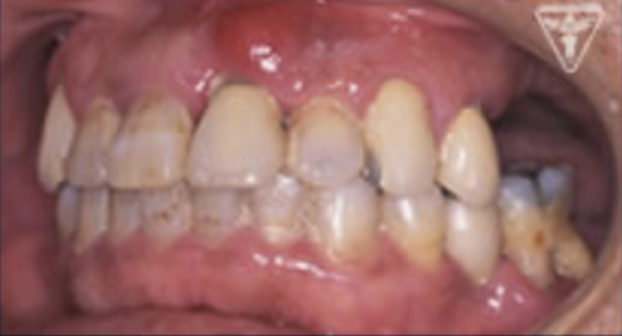

治療前

初診時での正面・側方・咬合面観を示します。